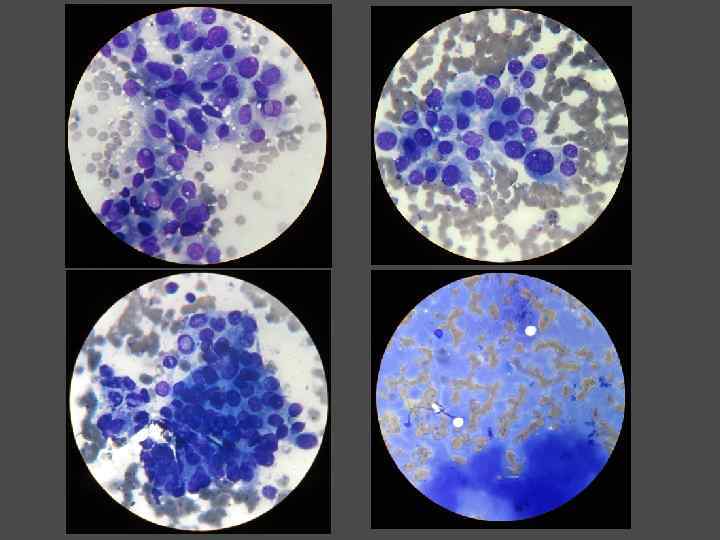

ПУНКЦИОНАЯ ТОНКОИГОЛЬНЯ АСПИРАЦИОННАЯ БИОПСИЯ (ПТАБ)

ПУНКЦИОНАЯ ТОНКОИГОЛЬНЯ АСПИРАЦИОННАЯ БИОПСИЯ (ПТАБ)

ИНТЕРПРЕТАЦИЯ РЕЗУЛЬТАТОВ ПТАБ ► Доброкачественный узел ► Рак ► Узел подозрительный на рак ► Воспалительной процесс ► Материал неинформативен